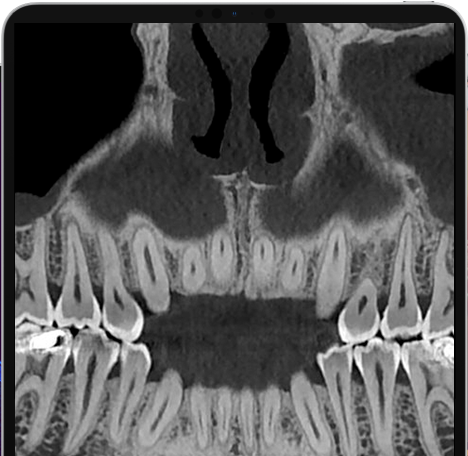

Veja exemplos de diagnósticos de imagem

Com apenas algumas etapas simples, o NNT pode processar os dados adquiridos durante a varredura para criar uma vasta gama de imagens, que fornecem informações detalhadas sobre a anatomia do paciente. Posteriormente, eles podem ser salvos em um relatório ou distribuídos com a versão Viewer do software. O NNT também oferece diferentes modos de aplicação voltados especificamente para implantologia, endodontia, periodontia, cirurgia maxilofacial e radiologia.